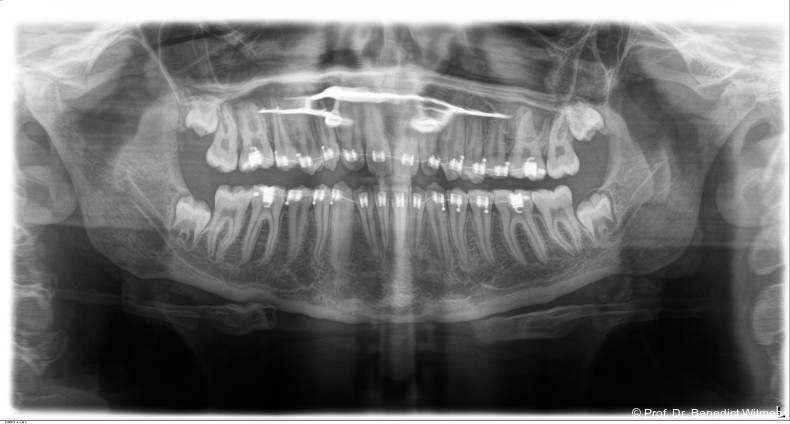

Klinisches Prozedere

Die initiale Behandlung erfolgte mit einer CAD/CAM Hybrid Hyrax zur Expansion des Oberkiefers, verankert an zwei paramedianen Miniimplantaten (Abb. 4, Benefit, 2,0 x 9,0 mm). Anstelle klassischer Molarenbänder wurden Shells (geklebte Kappen) verwendet, wodurch die beiden Schritte Separieren und Anpassen von Molarenbändern entfallen. Die Miniimplantate und die Apparatur wurden dank eines Inser­tionsguides in nur einer Sitzung eingesetzt.

Die Shells wurden mit lichthärtendem Kom­posit befestigt. Nach Expansion des Oberkiefers (Abb. 5a–f) erfolgte eine Retentionsphase von neun Monaten, in der die Hybrid Hyrax in situ belassen wurde.

Nach dieser Rentionszeit wurde die Hybrid Hyrax entfernt und ein Scan zur Herstellung der Molarenintrusionsapparatur (digitale Mause­falle) durchgeführt. Die beiden Miniimplantatköpfe lassen sie dabei sehr gut scannen, so­genannte Scan-Bodies sind in der Regel nicht mehr notwendig. Die digitale Mousetrap-­Appa­ratur besteht aus zwei Teilen (Abb. 6):

Der erste Teil ist ein TPA (bzw. Horseshoe-­Arch) mit Shells auf den ersten oberen Molaren sowie mesialen und distalen Extensionen auf den zweiten Prämolaren und den zweiten Molaren. Der TPA besitzt zudem kleine Extensionen zur späteren Befestigung von Power­chains oder NiTi-Federn. Zwischen TPA und palatinaler Mukosa sollte ausreichend Abstand eingeplant werden, um Druckstellen und Irritationen nach erfolgreicher Intrusion zu vermeiden. Die zweite Struktur wird üblicherweise an zwei oder drei Miniimplantaten im Gaumen fixiert. Sie umfasst ein H-förmiges Gerüst mit kleinen Extensionen zur Befestigung der Powerchains oder NiTi-Federn. Der biomechanische Kraftvektor ist auf die kranial (superior) positionierten Miniimplantate mit dem H-Gerüst ausgerichtet. Die erforderliche Intrusionskraft wird mit mindestens 200 g pro Seite avisiert. Die Kraft kann sowohl mittels Zugfedern oder elastischen Ketten appliziert werden, klinisch empfehlenswerter erscheinen jedoch Federn, da sie nicht bei jedem Termin gewechselt werden müssen. Aufgrund der starren Konstruktion des TPA werden Nebenwirkungen wie Kippungen der posterioren Zähne während der Kraft­applikation verhindert. Zur zusätzlichen Verankerung wurde in diesem Fall ein posteriores Benefit Direct-Implantat inseriert. Mittels der Mausefalle konnte der offene Biss erfolgreich innerhalb von acht Monaten korrigiert werden (Abb. 7a–f).

Nach erfolgreicher Expansion und Molaren­intrusion wurde eine Multibracket-Therapie zur Ausformung und Koordination der Zahnbögen durchgeführt (Abb. 8a–f). Nach Abschluss der aktiven Behandlungsphase wurden die Apparaturen entfernt und festsitzende Retainer im Ober- und Unterkiefer eingesetzt (Abb. 9a–k).